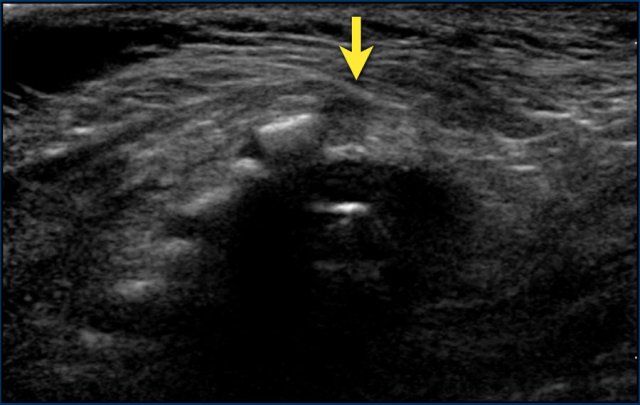

Three-day-old girl with a red stain on the lower back, a tuft of hair and a dimple.

US shows a tract from the skin towards the dural sac at the S1-S2 level, compatible with a dorsal dermal sinus .

The conus medullaris is at a normal level and there is no other intraspinal pathology present.

Dermal sinus tracts are especially important lesions to recognize because they can extend to the spinal canal and represent an increased risk of infection such as meningitis and spinal cord abscess.